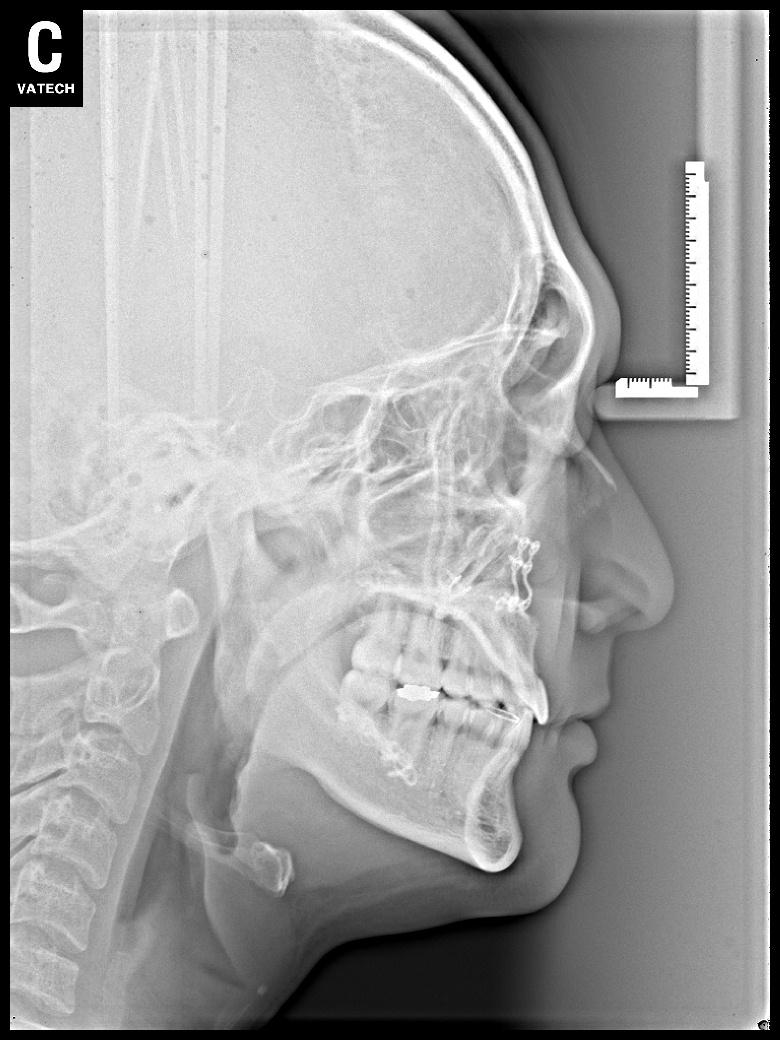

치료 전 사진입니다.